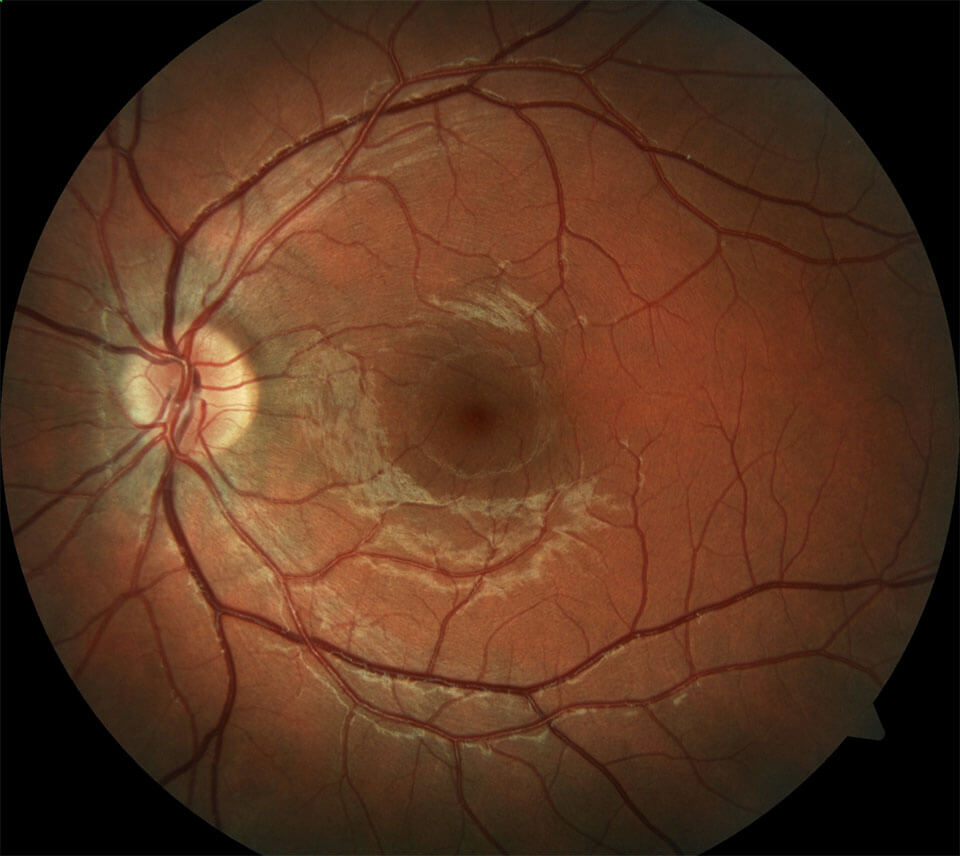

Изображения и анатомия сетчатки глаза

Раздел: Визуальный дайджест